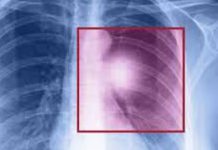

Новые дыхательные диагностические тесты на рак вступают в массовое тестирование

Сегодня команда специалистов-онкологов из онкологического исследовательского центра в Кембридже совместно со своими коллегами из медицинского центра Оулстоуна представ...

Новое исследование объясняет механизм усыпления раковых клеток иммунной системой

Эффективная борьба с зараженными раком клетками становится возможной лишь тогда, когда применяются наиболее проверенные и современные технологии и способы такой борьбы...